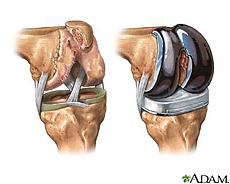

Knee replacement is surgery for people with severe knee damage. Knee replacement can relieve pain and allow you to be more active. Your doctor may recommend it if you have knee pain and medicine and other treatments are not helping you anymore.

When you have a total knee replacement, the surgeon removes damaged cartilage and bone from the surface of your knee joint and replaces them with a man-made surface of metal and plastic. In a partial knee replacement, the surgeon only replaces one part of your knee joint. The surgery can cause scarring, blood clots, and, rarely, infections. After a knee replacement, you will no longer be able to do certain activities, such as jogging and high-impact sports.